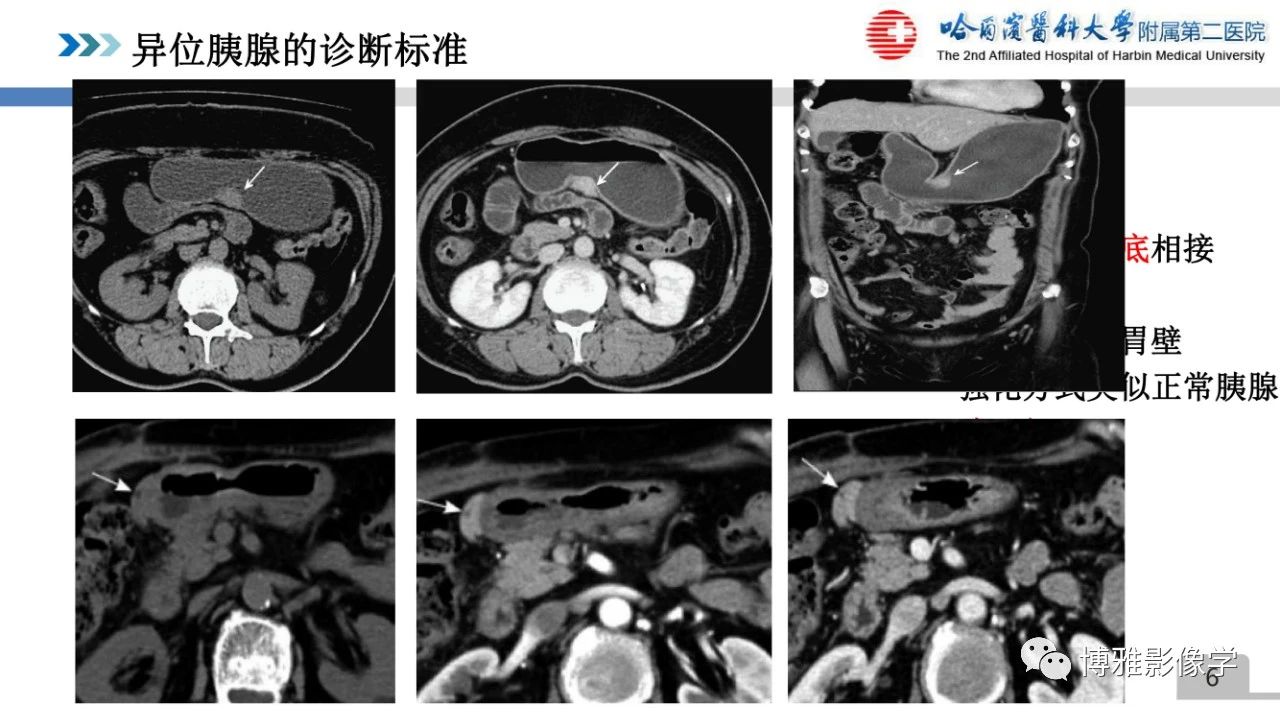

异位胰腺